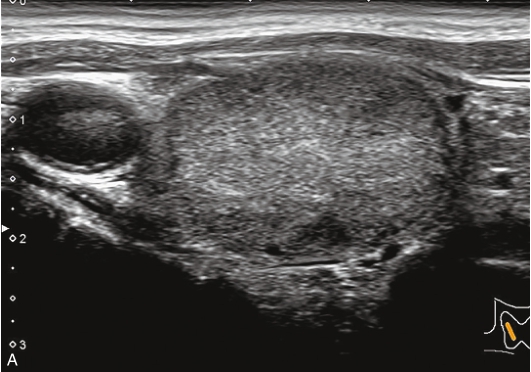

甲状腺形态基本正常,甲状腺实质回声稍增粗,分布尚均匀,甲状腺包膜尚光滑。甲状腺两叶内见多发结节,较大者位于左叶上极,呈类椭圆形,边界清楚,形态规则,纵横比<1,内部回声均匀,未见钙化,后方回声稍增强。CDFI显示左叶较大结节边缘可见丰富的条状血流信号,内部可见条状、点状血流信号,见图1-3-7。

图1-3-7 结节性甲状腺肿常规超声表现

A.常规超声图像;B.CDFI超声图像